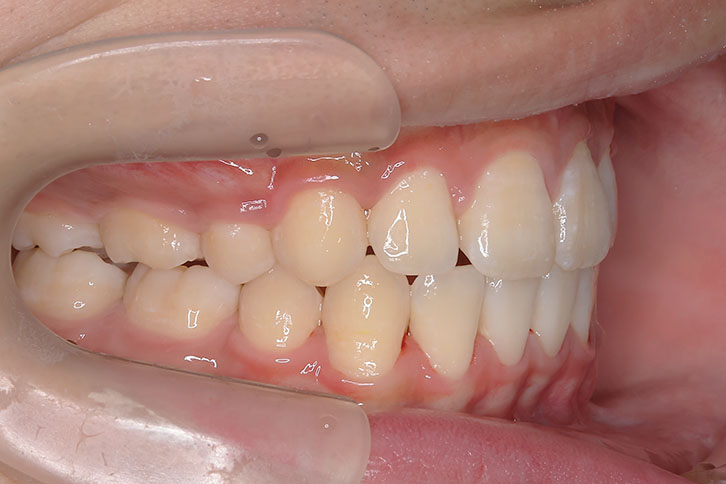

歯が重なっている、出っ歯を治したい 以前に治療した方からの紹介で来院した患者さんです。 上下顎前歯部の叢生(がたつき)、上下顎前歯の前方傾斜、 骨格的上顎前突傾向でした。 小児矯正で叢生の緩和を行い、 本格矯正で前方傾斜した前歯の改善を行いました。 マルチブラケット 動的治療期間 3年3か月 調整回数25回

平均来院間隔1.5か月に1度の来院でした。 治療後は後戻りの軽減するために、親知らず(第三大臼歯)の抜歯をお勧めしています。